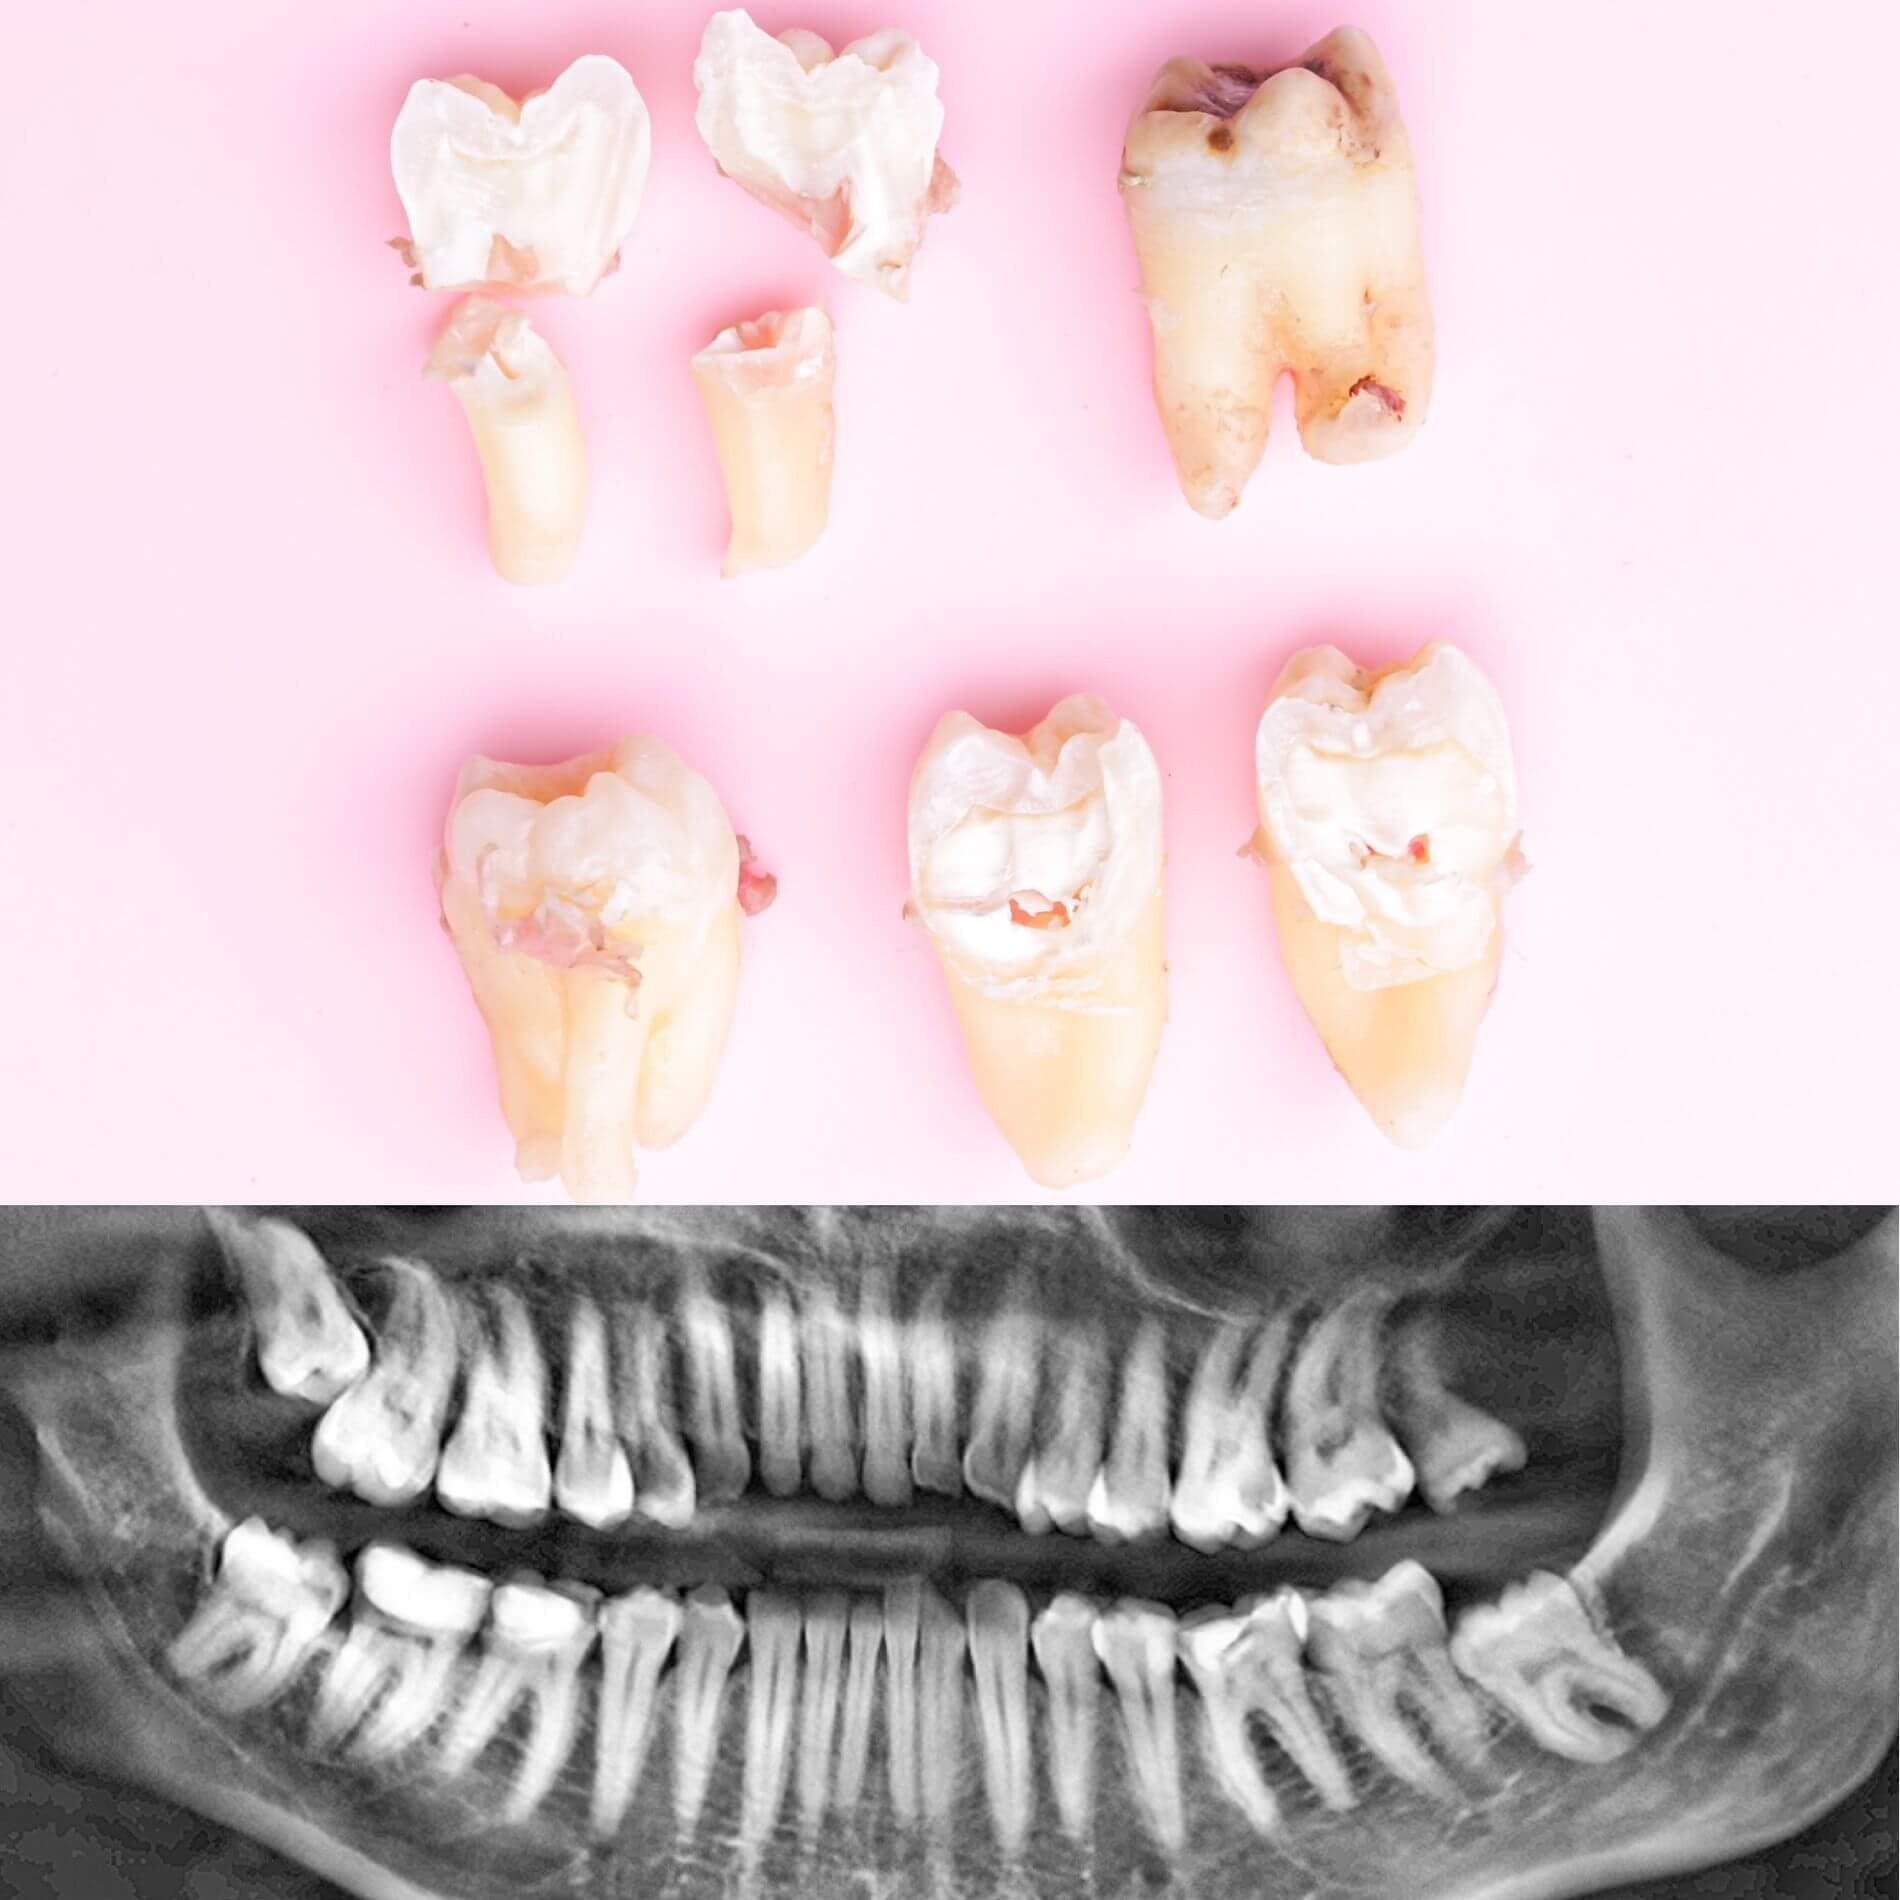

Галерея